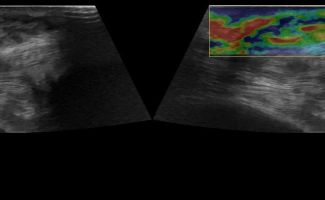

Η τεχνική του Έγχρωμου Doppler μελετάει την αγγείωση της βλάβης. Η τεχνική του Παλμικού Doppler μελετάει την παρουσία αρτηριακών ή φλεβικών στοιχείων εντός της βλάβης. Επίσης πολύ χρήσιμη είναι η Ελαστογραφική Μελέτη η οποία μελετάει τη σκληρότητας της βλάβης. Οι τεχνικές αυτές μας βοηθούν να χαρακτηρίσουμε αν η βλάβη είναι αγγειακού τύπου και αν έχει καλοήθη η ύποπτα χαρακτηριστικά.